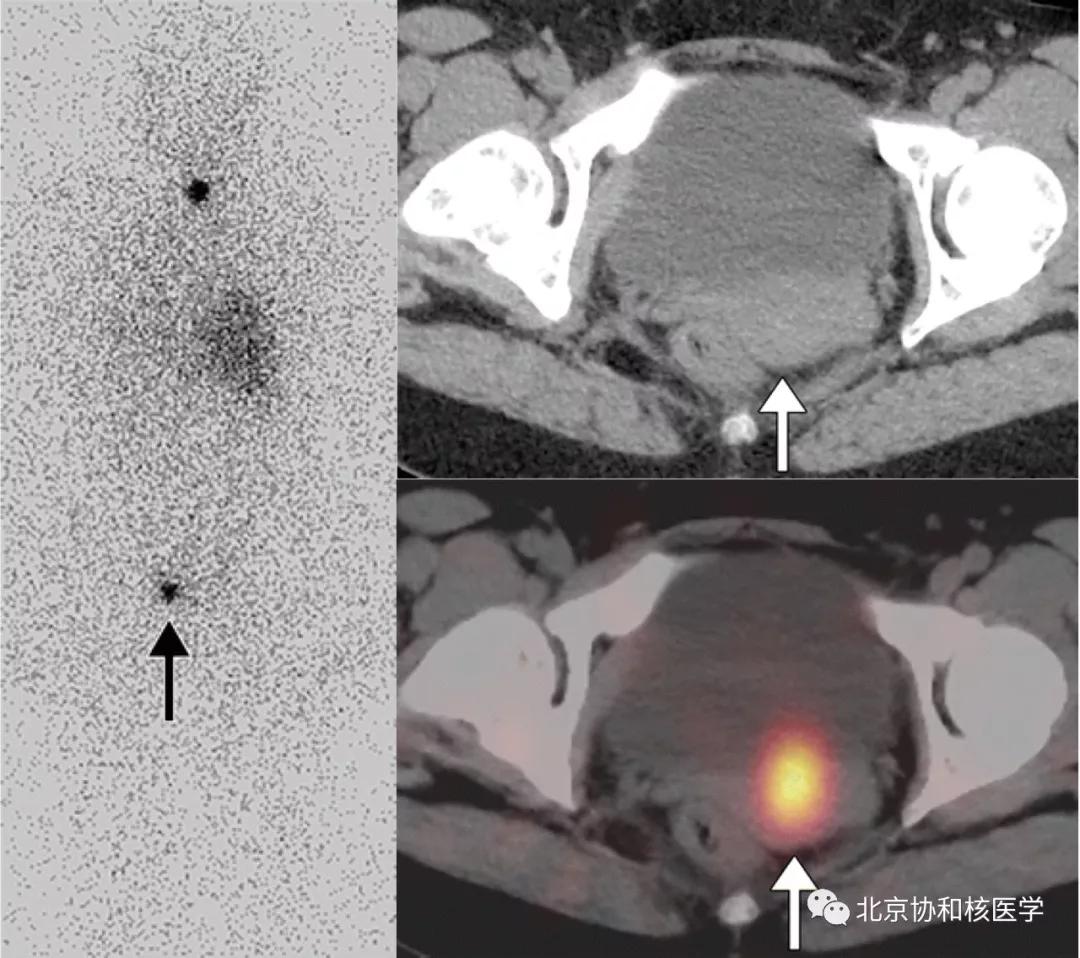

39岁女性,恶性卵巢甲状腺肿病史,行右侧卵巢切除术、甲状腺切除术、碘131治疗,碘扫可见残余甲状腺摄取、盆腔转移灶摄取及肝转移灶摄取:

鼻骨骨样骨瘤所致碘摄取,腹部另可见由于巨大肾囊肿所致碘异常摄取: